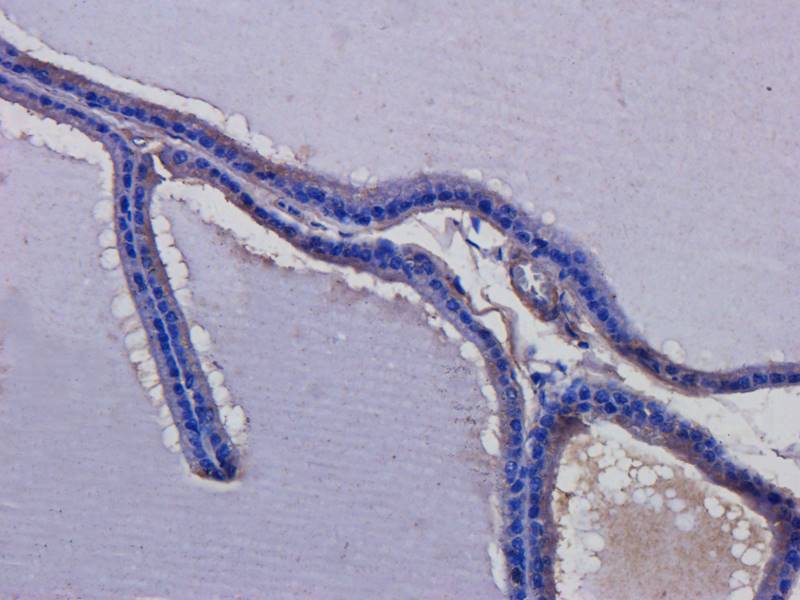

IHC staining of FFPE human brain with Ubiquitin antibody (clone PBQN-1). Required HIER: boil tissue sections in pH9 10mM Tris with 1mM EDTA for 10-20 min followed by cooling at RT for 20 min.